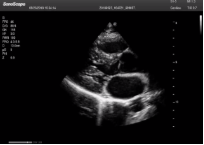

不同的探頭對應(yīng)于不同的臨床領(lǐng)域,不同的探頭頻率也應(yīng)用于不同的人體組織。超聲波在人體中的衰減與探頭頻率有關(guān),探頭頻率越高,穿透力越弱,分辨率越高,而探頭頻率越低,穿透力越強,分辨率越低。因此在檢查淺表器官時應(yīng)選用高頻探頭,而檢查深部臟器時則選用穿透性強的低頻探頭。

Mark點:每一把探頭都有一個mark點,是用于定位方向, mark點一側(cè)始終對應(yīng)著圖像S點(圖像箭頭標(biāo)識)一側(cè)。